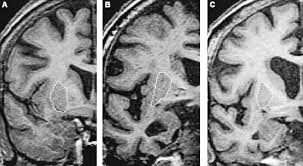

Lewy, the scientist who discovered them. Loss of substantia nigra hyperintensity on 7 tesla mri of parkinson's disease, multiple system atrophy, and progressive supranuclear palsy. Besides nuclear imaging methods, the clinical utility of structural neuroimaging with magnetic resonance imaging (mri) for differential comparison between dementia with lewy bodies and alzheimer's disease. You also might see things that aren't there, called hallucinations. Lbd is a term that covers two conditions that have similar. Protein deposits, called lewy bodies, develop in nerve cells in the brain regions involved in thinking, memory and movement (motor control). Certain nuclear scans of the brain, including positron emission. How is lewy body dementia (ldb) diagnosed? Dr michael firbank discusses his study using functional mri in lewy body dementia and alzheimer's disease at the newcastle university institute. Focal atrophy in dementia with lewy bodies on mri: Memory loss is not always an early symptom. Lewy body dementia (lbd) is a type of progressive dementia. Many people also experience changes in alertness including daytime sleepiness, confusion or staring spells.

Differences In Mr Features Of The Substantia Innominata Between Dementia With Lewy Bodies And Alzheimer S Disease Semantic Scholar

Differences In Mr Features Of The Substantia Innominata Between Dementia With Lewy Bodies And Alzheimer S Disease Semantic Scholar from d3i71xaburhd42.cloudfront.net